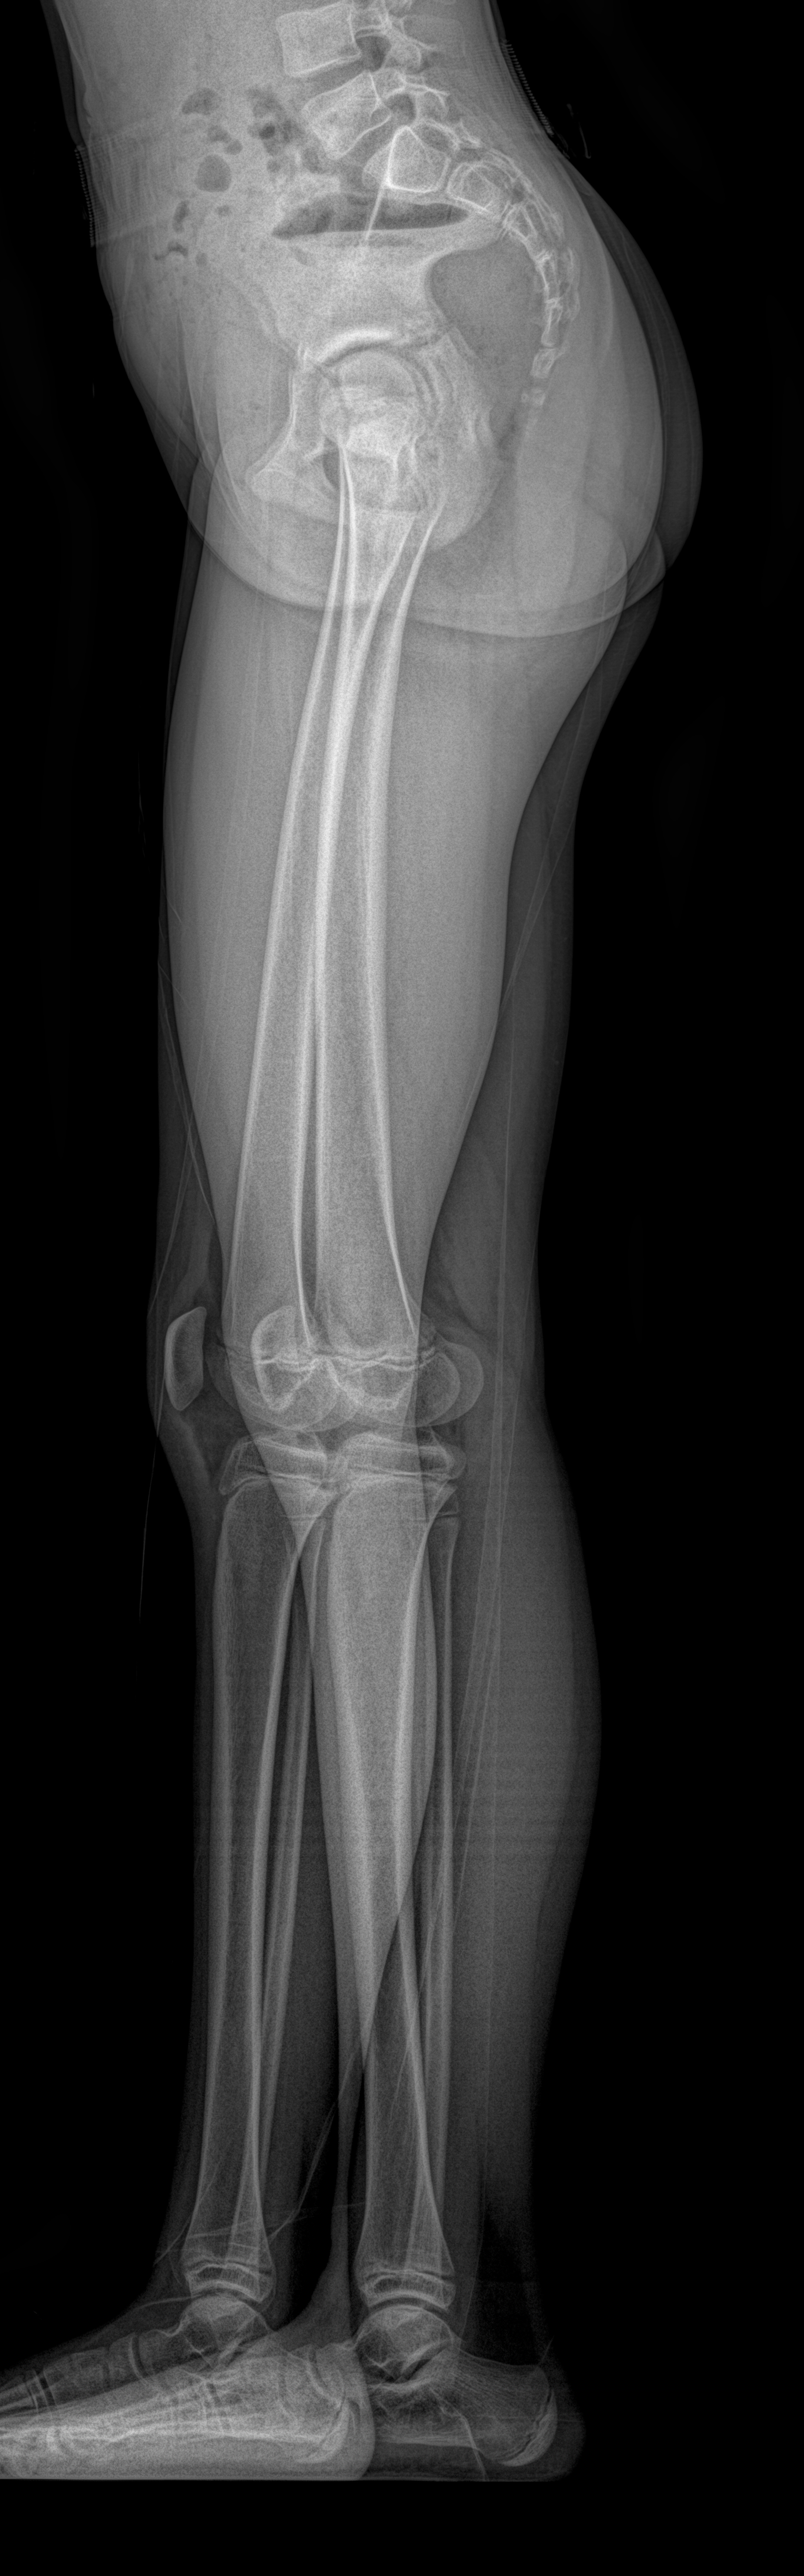

Bacak uzunluğu farklılıklarının milimetrik düzeyde ölçülmesini sağlar. Kliniğimizin EOS çekimleri, cerrahi ve ortopedik yaklaşımlarda doğru kararlar alınmasına katkı sağlar.